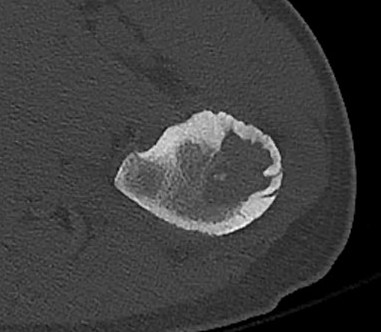

CT

Lucent lesion with nidus or calcification

Spinal lesion

- bone expansion

- intralesional stippled ossification